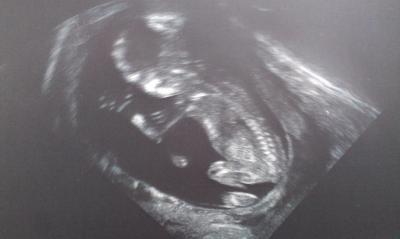

Einen wunderschönen guten Abend zusammen. Ich wollte mal kurz von meinem gestrigen Arzttermin berichten. Nach langen 4 Wochen Wartezeit durften wir unser Kleines endlich wiedersehen. Es hat fleißig gestrampelt, sich bewegt und gedreht, aber man hat die Hände mit Fingern sowie Füße & Zehen trotzdem genau erkannt. Es ist bei 13+2 jetzt 7,25 cm groß und zeitgerecht entwickelt Das Geschlecht war noch nicht zu erkennen. Habe gleich 4 Bilder bekommen, aber nur eins ist richtig scharf. Das dürft ihr auch gerne sehen :-) Leider habe ich jetzt Eisenmangel und muss künftig Tabletten nehmen. Außerdem wurde ich gleich gegen Grippe geimpft. Jetzt werde ich viel entspannter in die nächsten Wochen kugeln. Nächster Termin ist am 27.2.

Bild zu Große Erleichterung nach gestrigem FA-Termin - Forum für August - Mamis

Das klingt super und freut mich sehr für dich Das Bild ist total cool :-)

Oh prima... das Bild ist echt toll, sitzt da Wie ein Frosch und winkt. Süß.

Wow das klingt ja super und das Foto ist auch total toll - man erkennt sogar schon die Wirbelsäule Ich freu mich wirklich sehr für Euch!!!